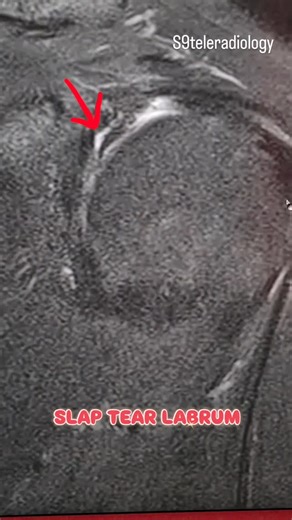

S9TELERADIOLOGY on Instagram: "SLAP (Superior Labrum Anterior

…

Type 2 SLAP Tear

7.1K views

Dec 30, 2015

YouTube

CTisus